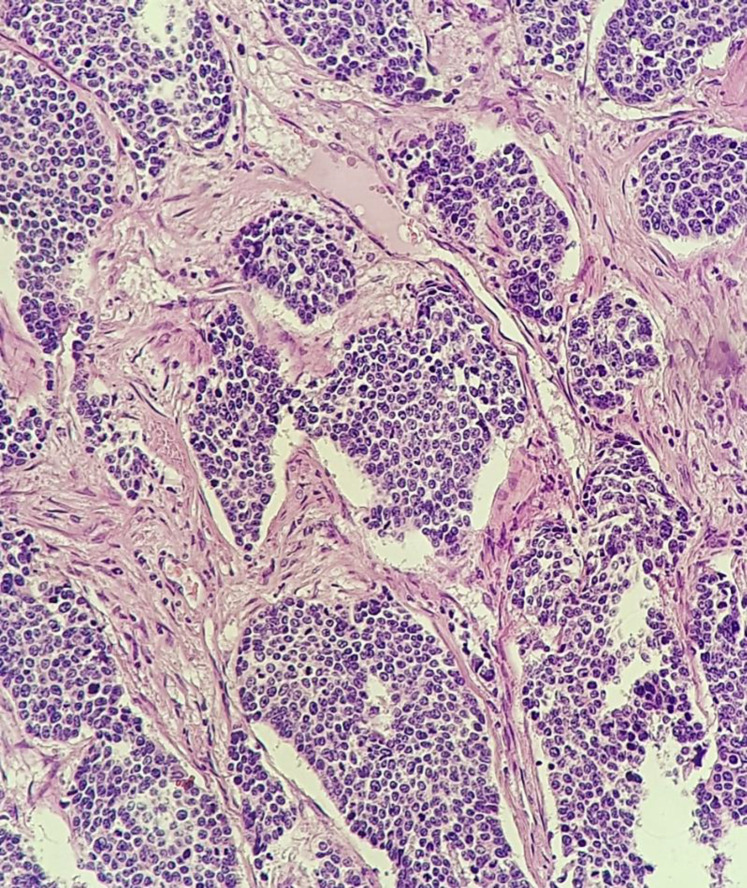

Background: Small cell carcinoma of cervix (SCCC) is a rare disease. SCCC is highly invasive and prone to distant metastatic spread and lymph node involvement. Here we aim to present a patient and her treatment.

Case presentation: We report 47-year-old patient with history of breast cancer manifesting with abnormal vaginal bleeding diagnosed with SCCC. Patient underwent radical hysterectomy and bilateral salpingo-oophorectomy. Then, she received adjuvant chemoradiation postoperatively.

Conclusion: Small cell carcinoma of cervix is an aggressive form of cervical cancer with poor prognosis. Optimal treatment remains unsettled.